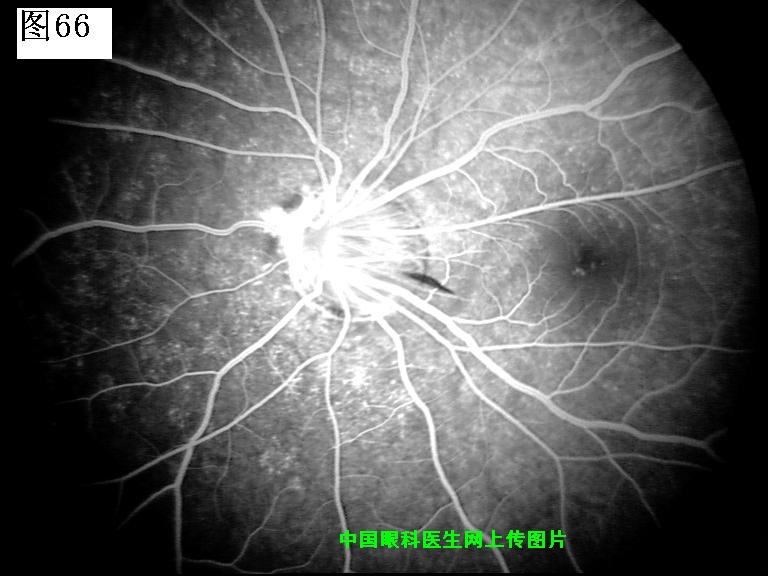

65 66 67 68